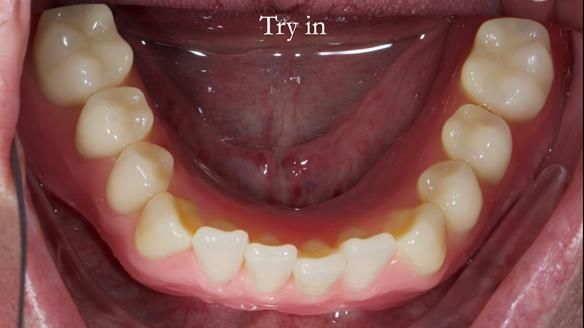

Welcome to my Newsletter 57, where I show the making and fitting of complete dentures supported by upper and lower dental implants for Alisdair. This issue provides a comprehensive overview of the entire protocol workflow.

The detailed clinical situation and treatment process are outlined below, with clinical work provided by me and technical work by Rowan Garstang. New complete implant supported complete dentures were made. The new upper denture had ‘almost’ full palatal extension for the non-splinted implants following ITI guidelines. A decision was reached to retain the worn Kerator attachments, as their removal could potentially accelerate implant failure. The treatment spanned five visits for denture fitting and one review. Alisdair expressed great satisfaction with the treatment, noting a significant enhancement in his overall quality of life.